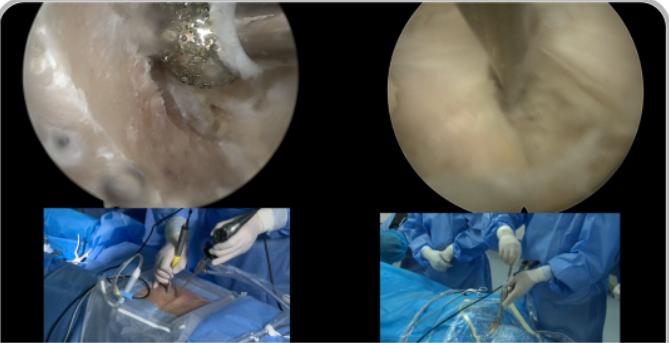

山東奧蘇本UBE/BESS雙通道脊柱內(nèi)鏡微創(chuàng)手術(shù)系統(tǒng)生產(chǎn)廠家產(chǎn)品說明:

雙通道脊柱內(nèi)鏡技術(shù)(BESS/UBE)手術(shù)適應(yīng)癥

1. 普通椎間盤突出、極外側(cè)間盤突出;

2. 中央椎管狹窄、側(cè)隱窩狹窄、椎間孔狹窄;

3. 頸椎、腰椎、胸椎的退行性形變;

4. 退行性滑脫(BE-TLIF) ;

5. 腰椎翻修病例;

6. 神經(jīng)根型頸椎病、脊髓型頸椎病